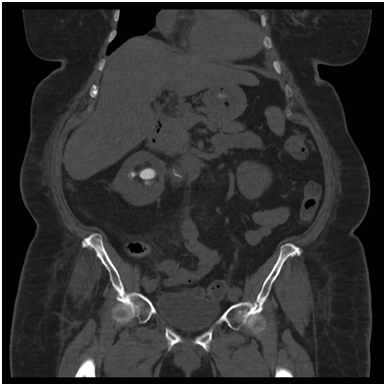

Typically, it presents non-specifically and similar to pyelonephritis, with flank pain, fever, haematuria and lower urinary tract symptoms [1-3]. XGP rarely affects both kidneys [4,5]. As in this case, a significant portion of patients have malignancy considered in the differential [1,3,5]. The optimal diagnostic modality has been cited as computed tomography (CT) [1,3]. Its advantages are that it can isolate significant disease in the majority of cases and also demonstrate associated findings such as hydronephrosis, renal parenchymal collections and abscess [1,2] (Figure 2)

The progression of XGP can be divided into three stages, stage 1, where inflammation is confined to the kidney. Perinephric fat is affected in stage two and finally in stage three, the inflammation affects retroperitoneum [2,4]. This case reflects the initiation of the pathophysiological process at the pelviureteric junction. The treatment of advanced XGP is frequently cited as nephrectomy [1,2,5], although cases where antibiotics have been successful have been cited [1,2,5]. Surgical success can also been improved with pre-operative and post-operative antibiotic use [1,5] The prognosis, with treatment of XGP is usually favourable, with rare cases of mortality associated with operative complication, such as sepsis [1,3] (Figure 3).

Figure 3: CT Nephrostogram demonstrating stricturing of the PUJ.